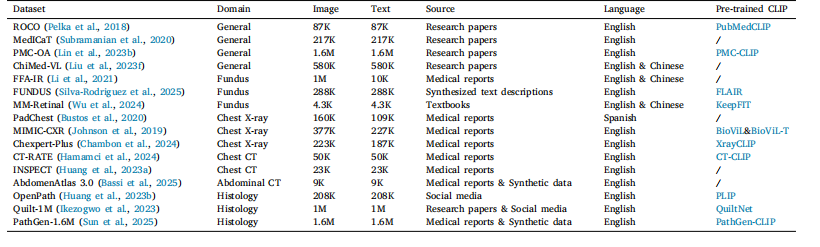

Table 1Summary of publicly available medical image–text datasets

表1 公开可用的医学图像-文本数据集概述